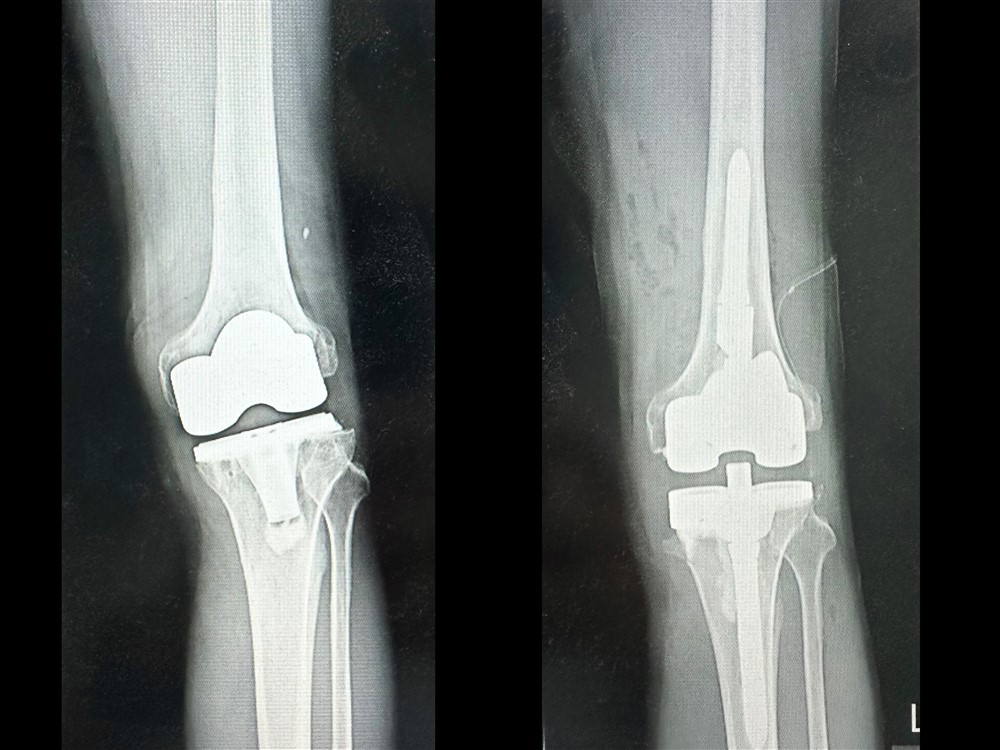

林先生經由親友介紹轉到台中慈濟醫院關節中心,趙子鎔醫師的門診。經X光與電腦斷層掃描結果顯示,林先生原本置換的人工關節角度出現偏差,導致膝關節軸向錯位、受力不均。趙醫師說明,人工關節應與人體重心軸線垂直,但病人術後角度卻反向歪了約十度,造成走路一踩就歪,膝蓋反覆發炎積水,當然會持續疼痛。

趙子鎔醫師與林先生反覆分析溝通後,進行「人工關節翻修再置換」手術,透過電腦斷層影像規畫,重新調整關節角度與力學軸線。術後第二天,林先生便能下床行走,一個月後腫脹消退,不再反覆積水,已經能獨自行動,甚至可以搭公車回診。他開心表示:「不再腫、不再痛,走路終於又有力量,非常感謝趙醫師。」

(左)人工膝關節的角度偏差,走路一踩就歪;(右)經過趙醫師翻修再置換手術之後,人工關節與人體重心軸線垂直。